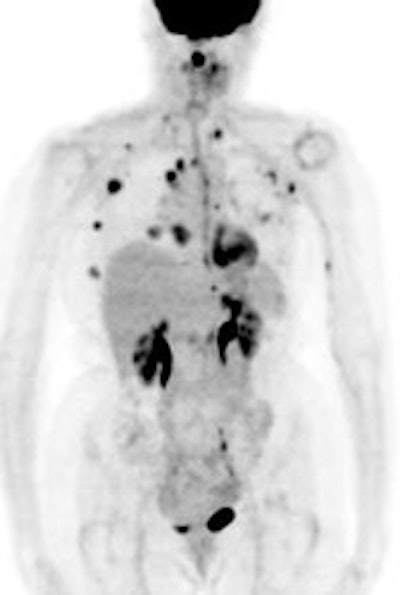

FDG PET exam results in breast cancer patient guide therapy: The patient shown below was a 40 year old female who had undergone lumpectomy and adjuvant chemo/radiation therapy for breast cancer. Ten months later the patient began to experience pain in the right shoulder. A bone scan and CT scan were interpreted as negative. The FDG PET exam revealed numerous foci of tracer accumulation within the right axilla and chest consistent with metastatic disease. As a result of the PET exam findings the patient was treated with another course of chemo/radiation therapy. The exam was performed on a Siemens ECAT EXACT PET scanner; 10 mCi FDG, and 5 bed positions. Case courtesy of Rush-Presbyterian-St. Luke's Medical Center, Chicago, IL and CTI. |